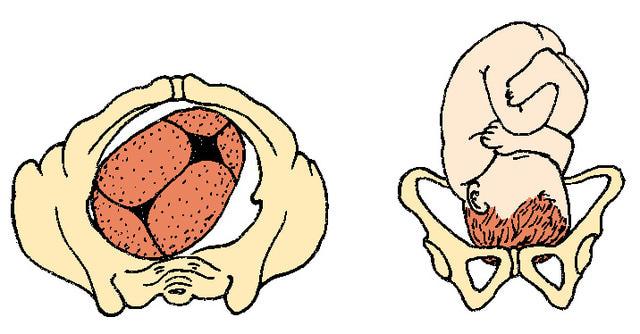

What is an ECV?

external cephalic version

What must be done before an ECV can be performed?

OR must be booked in case of an emergency birth.

What can a shoulder presentation lead to?

Shoulder Dystocia

What is shoulder dystocia?

obstructed labour whereby after the delivery of the head, the

anterior shoulder of the infant cannot pass below, or requires

significant manipulation to pass below, the pubic symphysis. It is

diagnosed when the shoulders fail to deliver shortly after the fetal head.